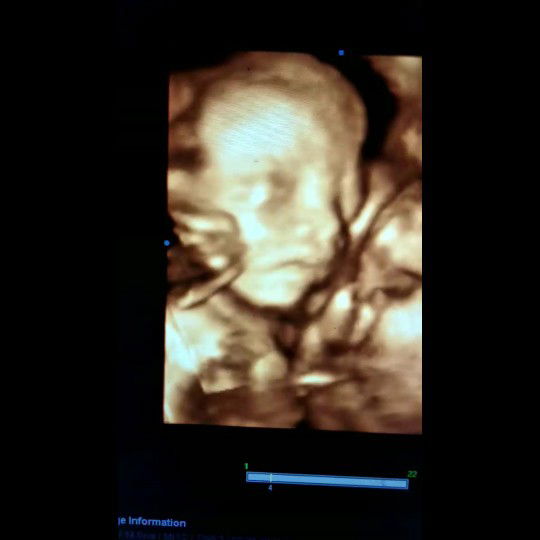

USG

21w lebih 4 hari ? Yang Hpl bulan Juni udah ngerasain apa aja Bun ??